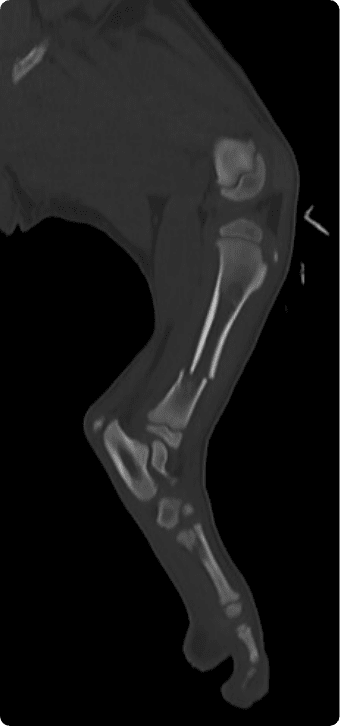

빠른 촬영속도를 통해 마취시간을 최소화 하며, 선명한 3차원 영상을 구현합니다.

골절, 골종양 등